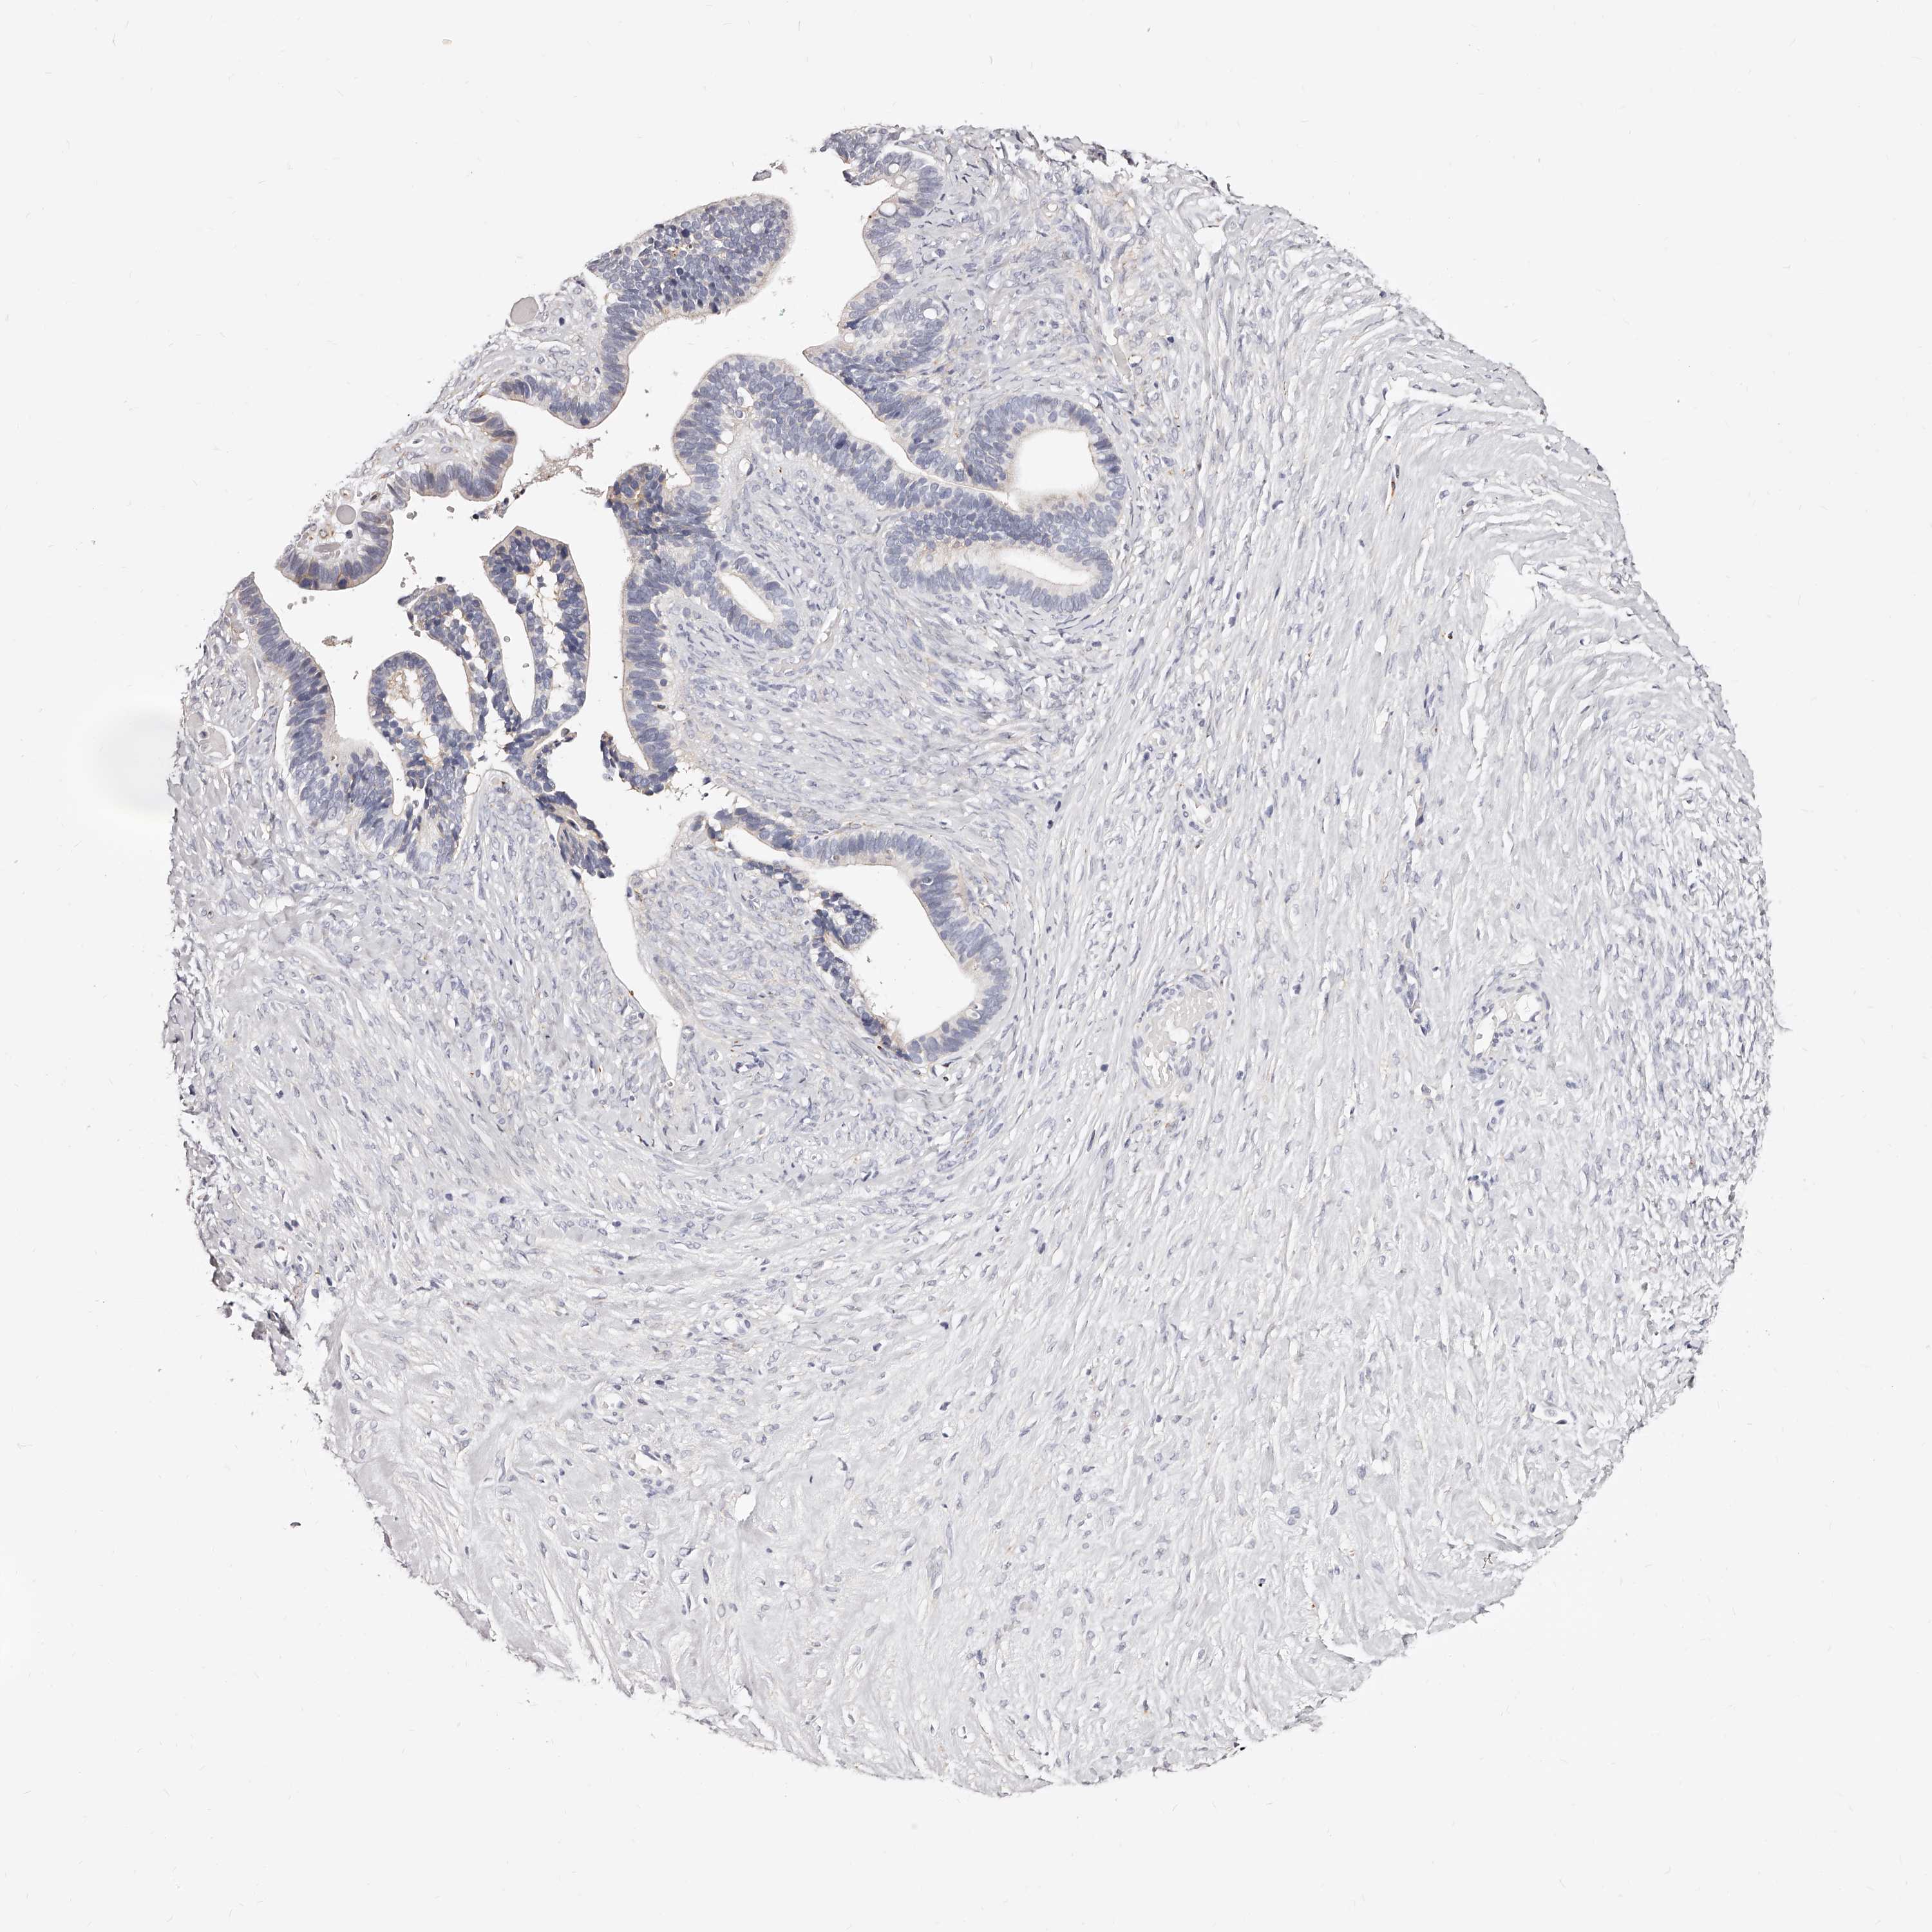

OVARIAN CANCER - Protein expressioni

A mouse-over function shows sample information and annotation data. Click on an image to view it in a full screen mode. Samples can be filtered based on level of antibody staining by selecting one or several of the following categories: high, medium, low and not detected. The assay and annotation is described here.

Note that samples used for immunohistochemistry by the Human Protein Atlas do not correspond to samples in the TCGA dataset.

Antibody stainingi

Antibody staining in the annotated cell types in the current human tissue is reported as not detected, low, medium, or high, based on conventional immunohistochemistry profiling in selected tissues. This score is based on the combination of the staining intensity and fraction of stained cells.

Each image is clickable and will lead to virtual microscopy that enables deeper exploration of all samples and also displays staining intensity scores, fraction scores and subcellular localization as well as patient and tissue information for each sample.

Antibody HPA028900

Antibody CAB002508

Cystadenocarcinoma, serous, NOS

Carcinoma, endometroid

Cystadenocarcinoma, mucinous, NOS

Carcinoma, NOS